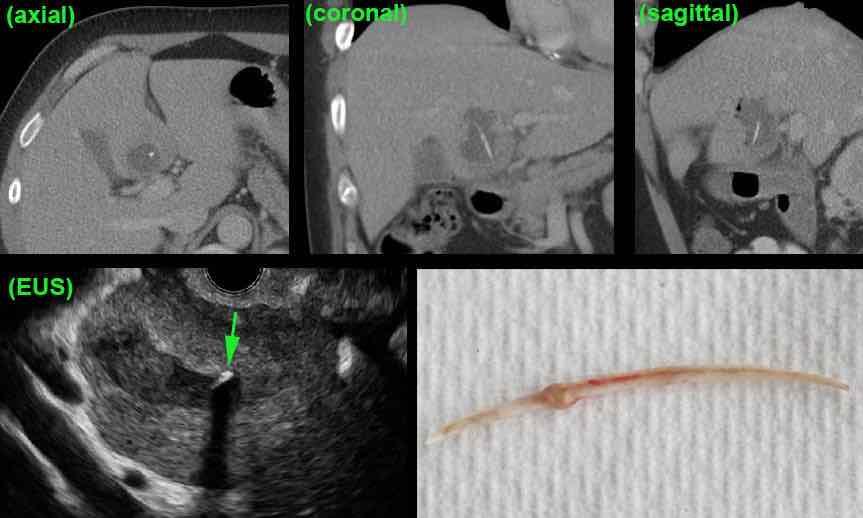

Bệnh nhân nữ 60 tuổi với sốt cao và nghi ngờ lâm sàng là viêm tụy.

CT scan cho thấy áp xe ở thùy vuông gan, chứa xương cá di chuyển từ dạ dày vào gan.

Siêu âm nội soi xác nhận xương cá nằm hoàn toàn trong áp xe gan (mũi tên), do đó không thể lấy qua nội soi.

Trong phẫu thuật, áp xe được dẫn lưu và xương cá được lấy ra.